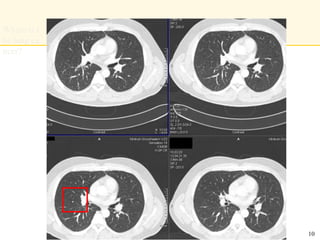

Where is t

he lung ca

ncer?